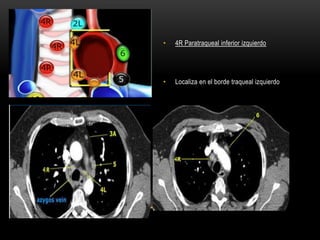

4R Paratraqueal inferior derecho.

• 4R Paratraqueal inferior izquierdo

• Localiza en el borde traqueal izquierdo

4R Paratraqueal inferiorderecho. • Borde superior: intersección de la vena innominada con la tráquea. • Borde inferior: borde inferior de la vena azigos.

• 4R Paratraquealinferior izquierdo • Localiza en el borde traqueal izquierdo